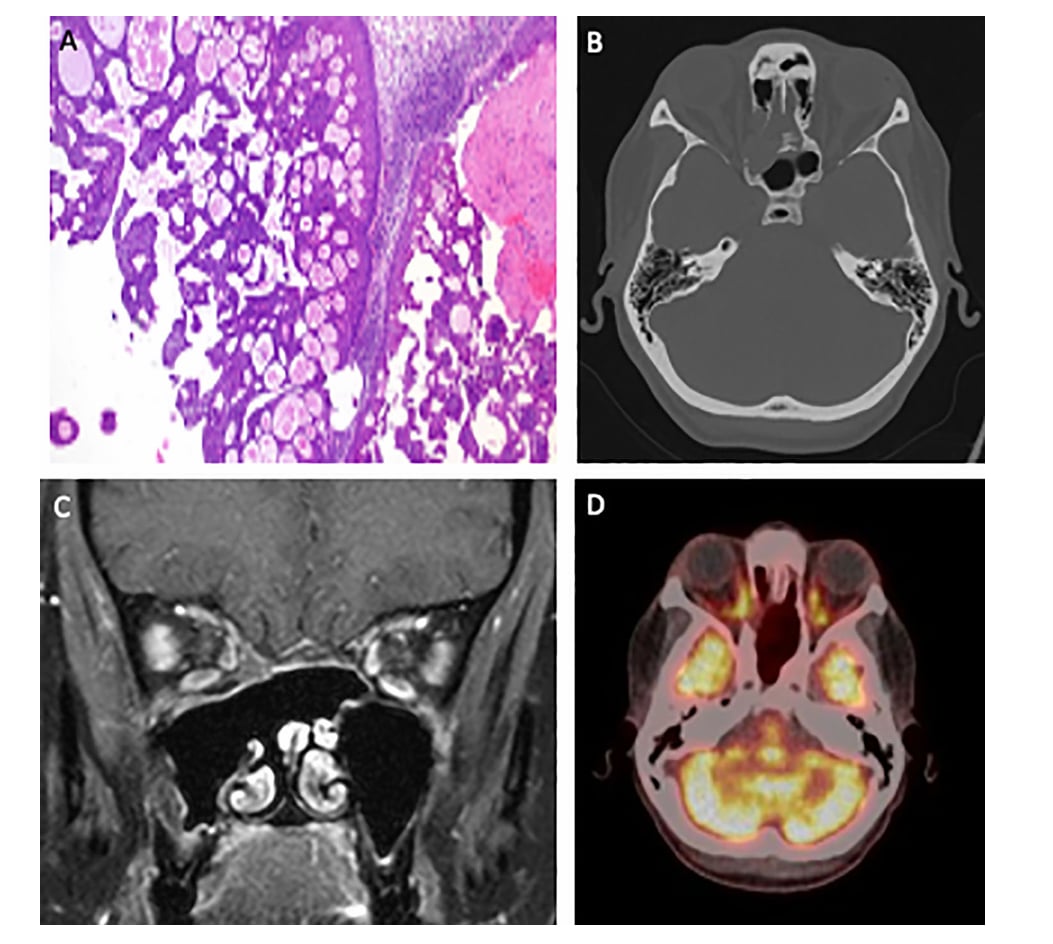

一名46岁的女性患者,在长达数年间因鼻窦占位被反复诊断为“倒生乳头状瘤”,并接受了多次手术。然而,病情持续进展,2023年影像检查显示肿瘤已侵犯眼眶骨。最终,通过基因检测,她被确诊为DEK::AFF2融合鼻旁窦癌。

面对这种罕见且棘手的癌症,肿瘤多学科团队决定采用新辅助化疗方案。患者接受了3个周期的顺铂(Cisplatin)联合吉西他滨(Gemcitabine)化疗。令人振奋的是,化疗后复查MRI显示,肿瘤竟然完全消失!鉴于前所未有的疗效,治疗方案调整为根治性放化疗以巩固效果。截至最新随访,PET-CT确认患者达到完全代谢性缓解,实现了无病生存。